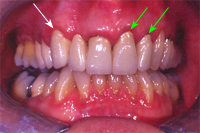

Im September 1983 wurde die viergliedrige Brücke auf zwei eigenen Zähnen und dem Implantat festsitzend zementiert (Kronenränder wie oben gesagt unter dem Zahnfleisch). Knapp 23 Jahre später sind bei den eigenen Pfeilerzähnen (weisse Pfeile, Abb. 4) sowie dem Implantatzahn (grüner Pfeil, Abb. 4) die Kronenränder sichtbar.

Ich bin mir auch sicher, dass die Zahnfleischrezession im Oberkiefer links (Abb. 6) zum Stillstand gekommen ist: Sie ist seit mehreren Jahren stabil. Die Tatsache, dass der Eckzahn rechts (Abb. 7, weisser Pfeil) keine Zahnfleischrezession, der mittlere und der seitliche Schneidezahn links (Abb. 7, grüne Pfeile) in der gleichen Brücke aber einen deutlichen Zahnfleischrückgang aufweisen, zeigt, dass nebst einer genetischen Komponente auch ein Zahnbürsten-traumatischer Einfluss an der Zahnfleischrezession im Oberkiefer links verantwortlich war.